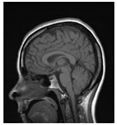

| Original Image | Marked Image | Encrypted Image (Chaotic) | Decrypted Image | Correlation between Extracted Blocks and Original Blocks |

![]() | ![]() PSNR = 35.99 dB SSIM = 0.97 | ![]() PSNR = 12.17 dB SSIM = 0.1035 | ![]() PSNR = 35.99 dB SSIM = 0.97 | ![]() |